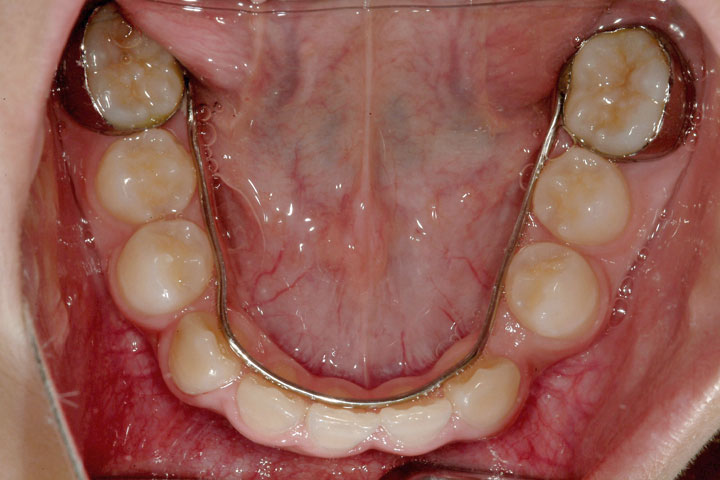

受け口を主訴に来院された幼稚園年長の女の子です。上顎前歯が未萌出であったため、その萌出を待って小学校2年生の時に矯正治療を開始いたしました。前歯部被蓋改善をリンガルアーチとチンキャップで行った後、定期観察を経てデーモンシステムで最終的に配列を行いました。下顎前歯が3本しかなく、一本の先欠(先天性欠損)を認めましたが、その空隙も閉鎖することができました。前歯被蓋の安定までに2年、その後中学1年生までの定期観察を経て、エッジワイズ治療期間で2年を要しました。